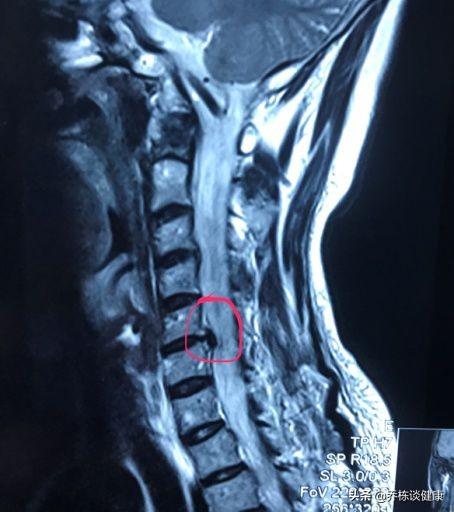

Le diagnostic de spondylose cervicale doit présenter des modifications de l'imagerie des lésions du rachis cervical, comme l'IRM, et s'accompagner des manifestations cliniques correspondantes, et le diagnostic ne peut être établi qu'en l'absence de l'une ou l'autre de ces manifestations. Le diagnostic ne peut être établi sur la base d'un seul élément.

Au sein de la spondylose cervicale, il existe un type agressif de spondylose cervicale appelé spondylose cervicale médullaire, car la hernie discale exerce une pression directe sur la moelle épinière, ce qui entraîne une dégénérescence de la colonne vertébrale. Si le type central de hernie discale cervicale est détecté lors de l'IRM et que la hernie est plus grave, il convient d'accorder une attention particulière à la protection des vertèbres cervicales, afin de ne pas freiner brusquement et brutalement, ou de ne pas soumettre le cou à une forte impulsion, et de ne pas présenter un mouvement de coup de fouet entraînant une paralysie, ce qui peut avoir des conséquences très graves.